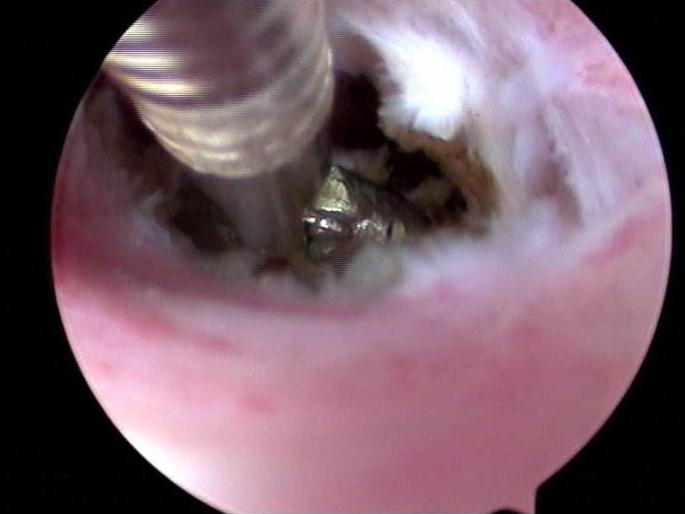

一般來說,單憑B超檢查并不能確診宮腔粘連,B超檢查只作為影像學上的診斷,并不是臨床診斷的金標準。要進一步確診,需要作宮腔鏡檢查,但是宮腔鏡具有侵入性,難免會對胎兒造成損傷,所以孕婦一般不主張進行宮腔鏡檢查。